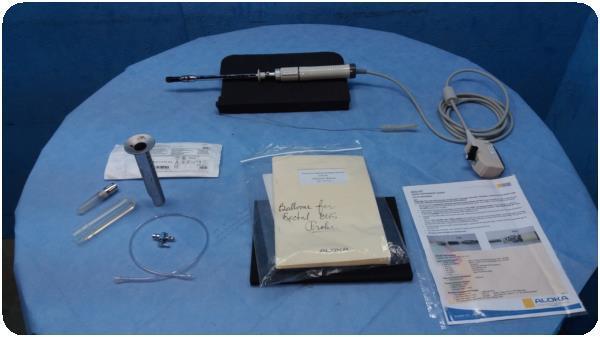

Aloka 3.5MHz Ultrasound Probe UST-979-3.5

Sale price$ 1,413.68

Aloka 7.UST-579T-7.55Mhz Ultrasound Probe

Sale price$ 2,640.38